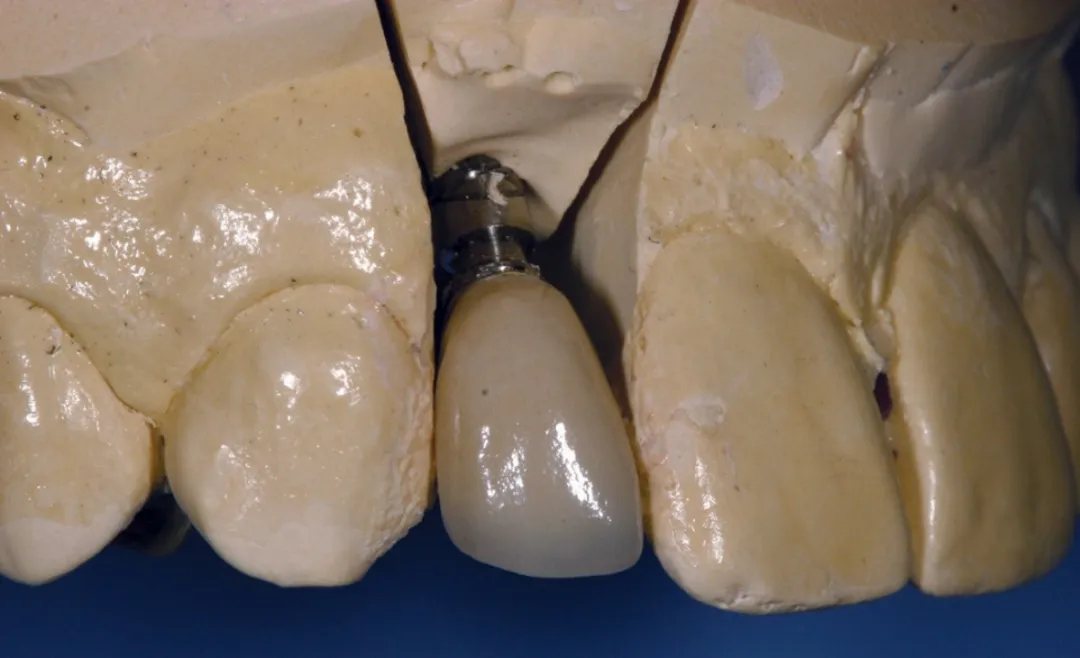

图 13 :试戴基台。

图 15 :石膏模型上试戴最终修复体。